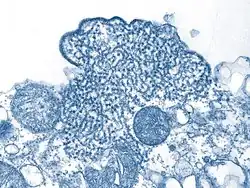

Microfotografía electrónica de transmisión (TEM) que muestra viriones de Nipah aislados del fluido espinal de un paciente